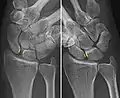

Dynamic instability: Increased scapholunate distance (between yellow lines) upon ulnar deviation of the wrist, but not otherwise.